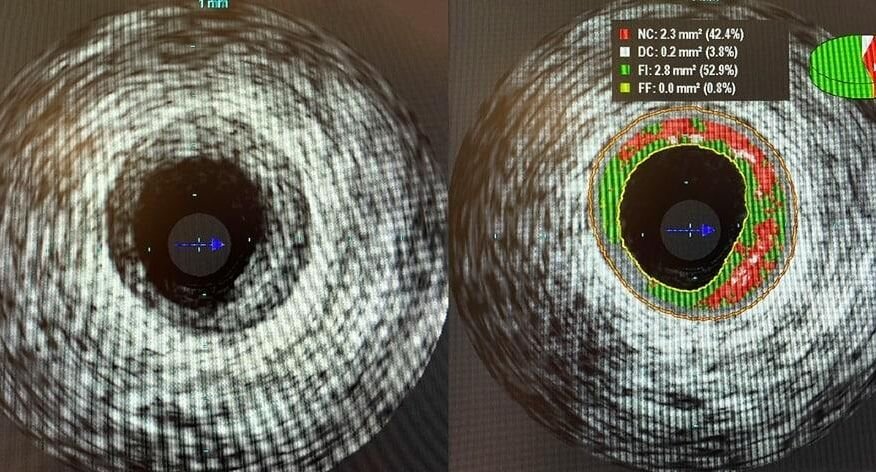

Новые виды внутрисосудистой хирургии стали доступны пациентам в МОНИКИ имени Владимирского. С помощью специального ультрасовременного оборудования хирурги смогут детально изучить пораженный участок сосуда.

Теперь врачи смогут получать 3D-изображение сосуда сердца, изучать структуру бляшки, измерять индекс давления кровотока. Это позволит предотвратить развитие острого инфаркта.

«С помощью оборудования мы получаем информацию, позволяющую с большей точностью определить дальнейшее лечение — необходимость медикаментозной терапии или стентирования», — рассказал заведующий отделом эндоваскулярного лечения сердечно-сосудистых заболеваний и нарушений ритма МОНИКИ Алексей Азаров.